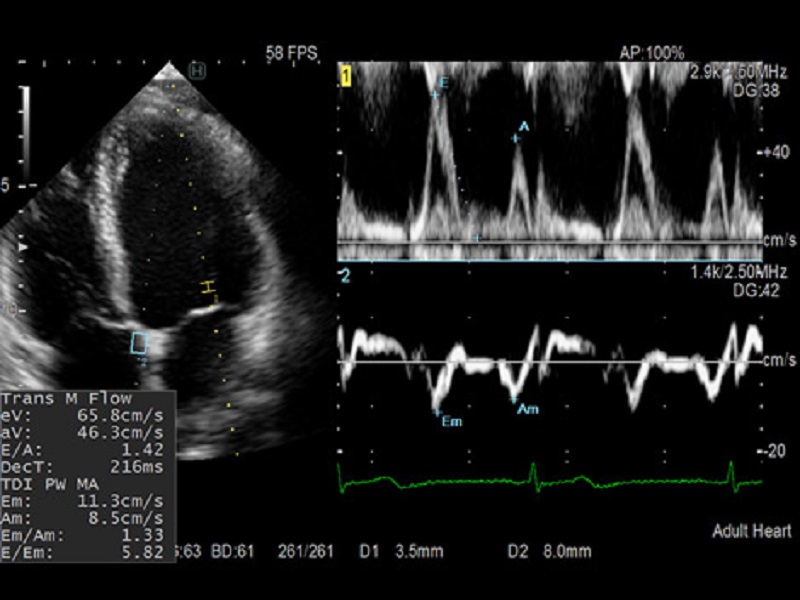

Dual Gate Doppler

- Collects Doppler waveforms from two locations during the same heart beat

- Enables faster and more accurate measurement of LV diastolic performance indicators

- Useful in diagnosis of fetal arrhythmia and Carotid stenosis

Dormed Hellas AR65 – Dual Gate Doppler Dormed Hellas AR65 – Breast RTE